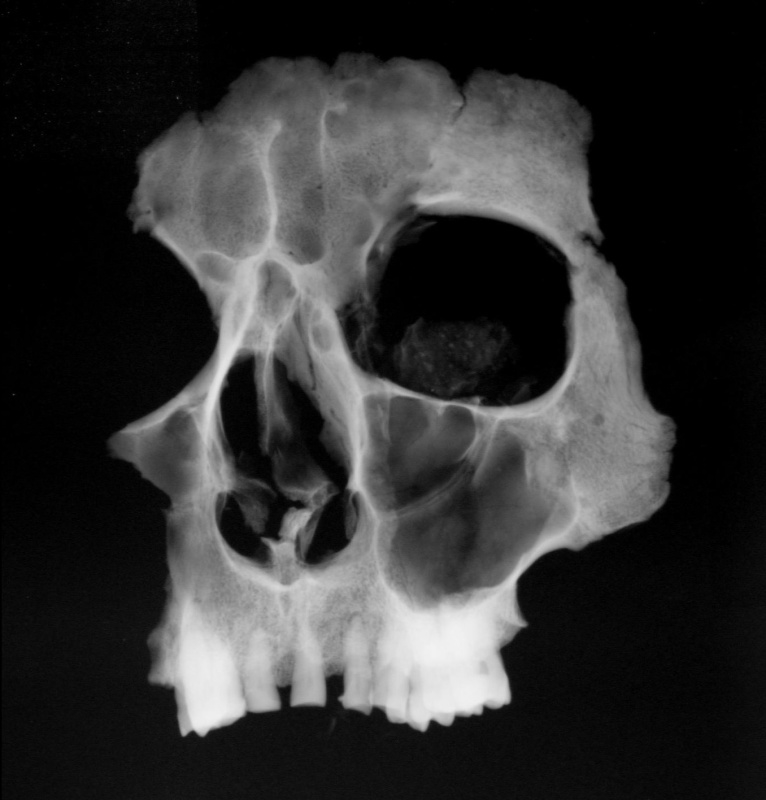

Biological research was performed at the workplace of the Anthropological Department of the National Museum where the X-ray, photographic and morphological documentation of the remains was completed.

After opening the metal box titled ‘Tycho Brahe 1901’, the content appeared comprising of the secondary placed bones of one individual (in non-anatomic order). During the first phase the biological samples were taken respecting the principles of the contamination minimizing. The content of the box was gradually removed. The funeral garment was the last located item. The skeletal remains were then assembled in anatomic order, which clearly indicated that the right upper half of the skeleton was strongly damaged and incomplete. The box also contained two glass vessels. The larger vessel included the remains of facial skeleton with beard and the authenticity certificate from Dr. Jindřich Matiegka from 1901. The smaller glass vessel contained the residues of organic material.

The total of 13 teeth remained from the upper jaw in situ. Teeth are more grinded on the right side of dental arch, which indicates that Tycho Brahe was right handed. Only six loose teeth remained from the lower jaw indicating the individual suffered from periodontitis.

In the area of the nasal opening (apertura piriformis) the residues of green shade were found as described by Jindřich Matiegka in his report. The colour caused by the presence of copper ions can indicate the use of nasal attachment. Nose and nasal bone injury, which the astronomer suffered in battle is not visible.